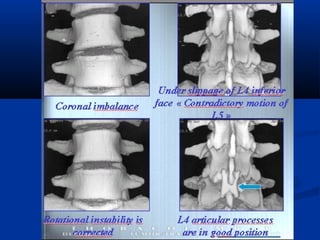

AA.. ΘΘέέσσηη ττοουυ ααρρθθρριικκοούύ

θθυυλλάάκκοουυ σσεε κκάάμμψψηη

BB.. ΣΣεε έέκκτταασσηη,, ηη άάννωω ααρρθθρριικκήή

ααππόόφφυυσσηη ττοουυ υυπποοκκεείίμμεεννοουυ

σσπποοννδδύύλλοουυ ππααρρεεκκττοοππίίζζεειι ππρροοςς

τταα εεμμππρρόόςς ττοονν ααρρθθρριικκόό θθύύλλαακκοο

ππρροοκκααλλώώννττααςς σσττέέννωωσσηη ττοουυ

μμεεσσοοππσσοοννδδυυλλίίοουυ ττρρήήμμααττοοςς